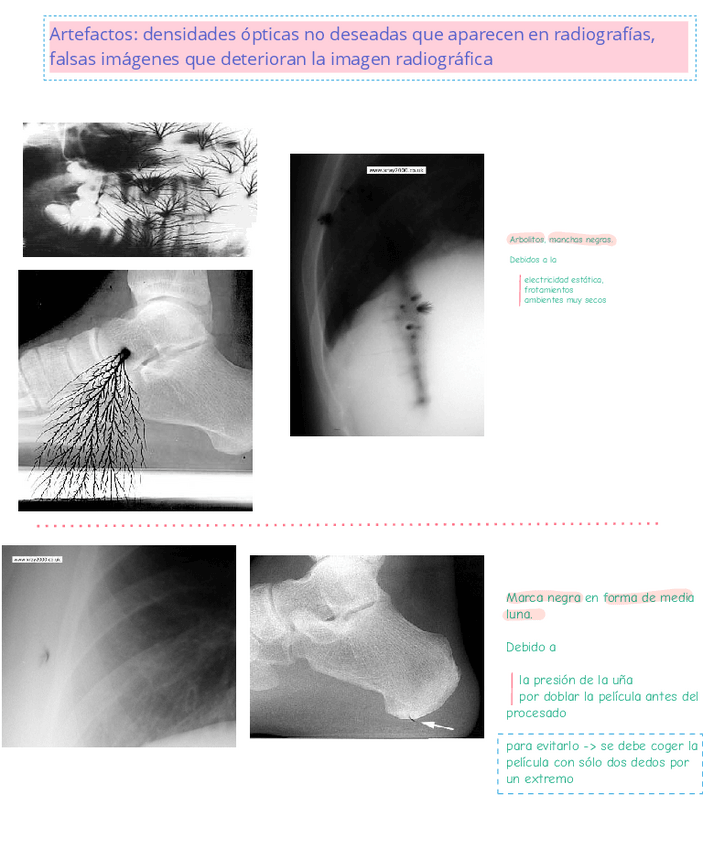

Apuntes - artefactos fundamentos .pdf